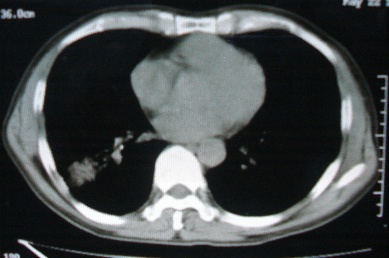

ct10716,男,59岁。发热咳嗽一天,咯血一次入院。

病灶中心有低密度,气体,病灶周围炎性浸润可能为肺脓肿,量体温、查个痰就是了,但肺脓肿一般都多少会有点兄水的。左肺下局部密度减低,小叶中心肺气肿。

右下肺病灶,边缘模糊,中心见低密度坏死区及气体影,结合病史较短,以发热为主,考虑右下肺脓肿,建议抗炎治疗后复查。